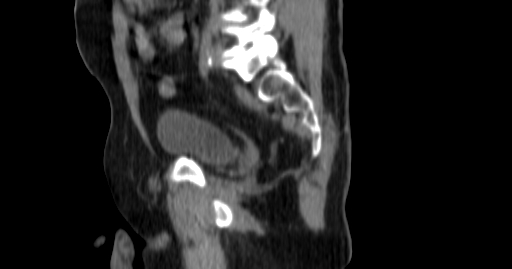

ClearRT® Images

Imaging Information

ClearRT®

Protocol

Pelvis-normal-FOV50cm

Scan Length

9 cm

KVCT Imaging Time

18 sec